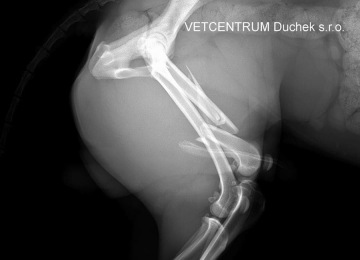

Přišel k nám s tříštivou zlomeninou stehenní kosti.

Maxíkova operace byla provedena v inhalační anestézii Isofluranem, před operací dostal Maxík nitrožilně antibiotika. Tříštivá zlomenina stehenní kosti, kde byly 4 fragmenty (úlomky), byla řešena nejprve fixací největšího fragmentu ke kosti dvěma cerklážemi a pak přemosťující ploténkou se sedmi šrouby. Cílem bylo zachovat osu končetiny, funkčnost kyčelního a kolenního kloubu a přiblížit úlomky co nejvíce ke kosti. Jak je vidět na pooperačním RTG snímku, krásně se to podařilo. Max bude brát ještě týden ATB, léky na bolest dle potřeby a modřina vzniklá během úrazu se mu bude mazat Heparoidem. Další RTG jsou plánovány 3-4 týdny po operaci. Zlomenina srůstá po operaci obvykle 6-8 týdnů.